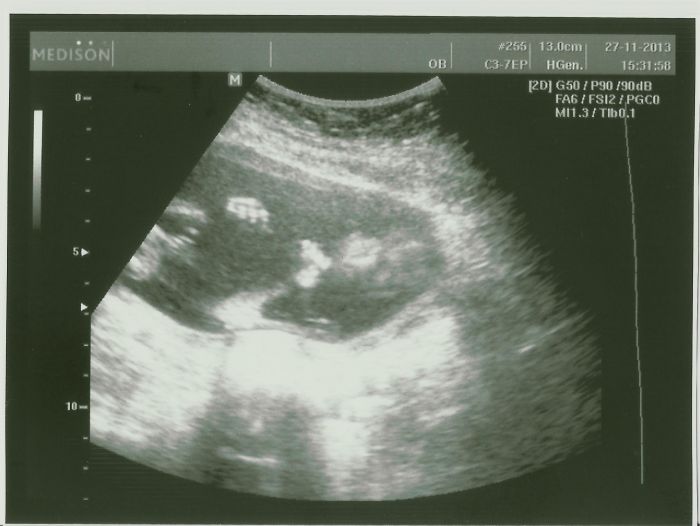

Tak jsem dnes byla na domluveném utz s manželem :) Budoucímu taťkovi se to moooc líbilo :) Malej se drbal na hlavě a pak se začal neuvěřitelně kroutit :D Bylo to bezva a oba jsme si to užili :) Díky Bohu za tak skvělou doktorku

[396264] Eviku, to jsou kouzelny obrazky! :-)) Ty rucicky a nozky, nadhera!

[396267] Děkuju Evi :) Malej se dneska opravdu snažil